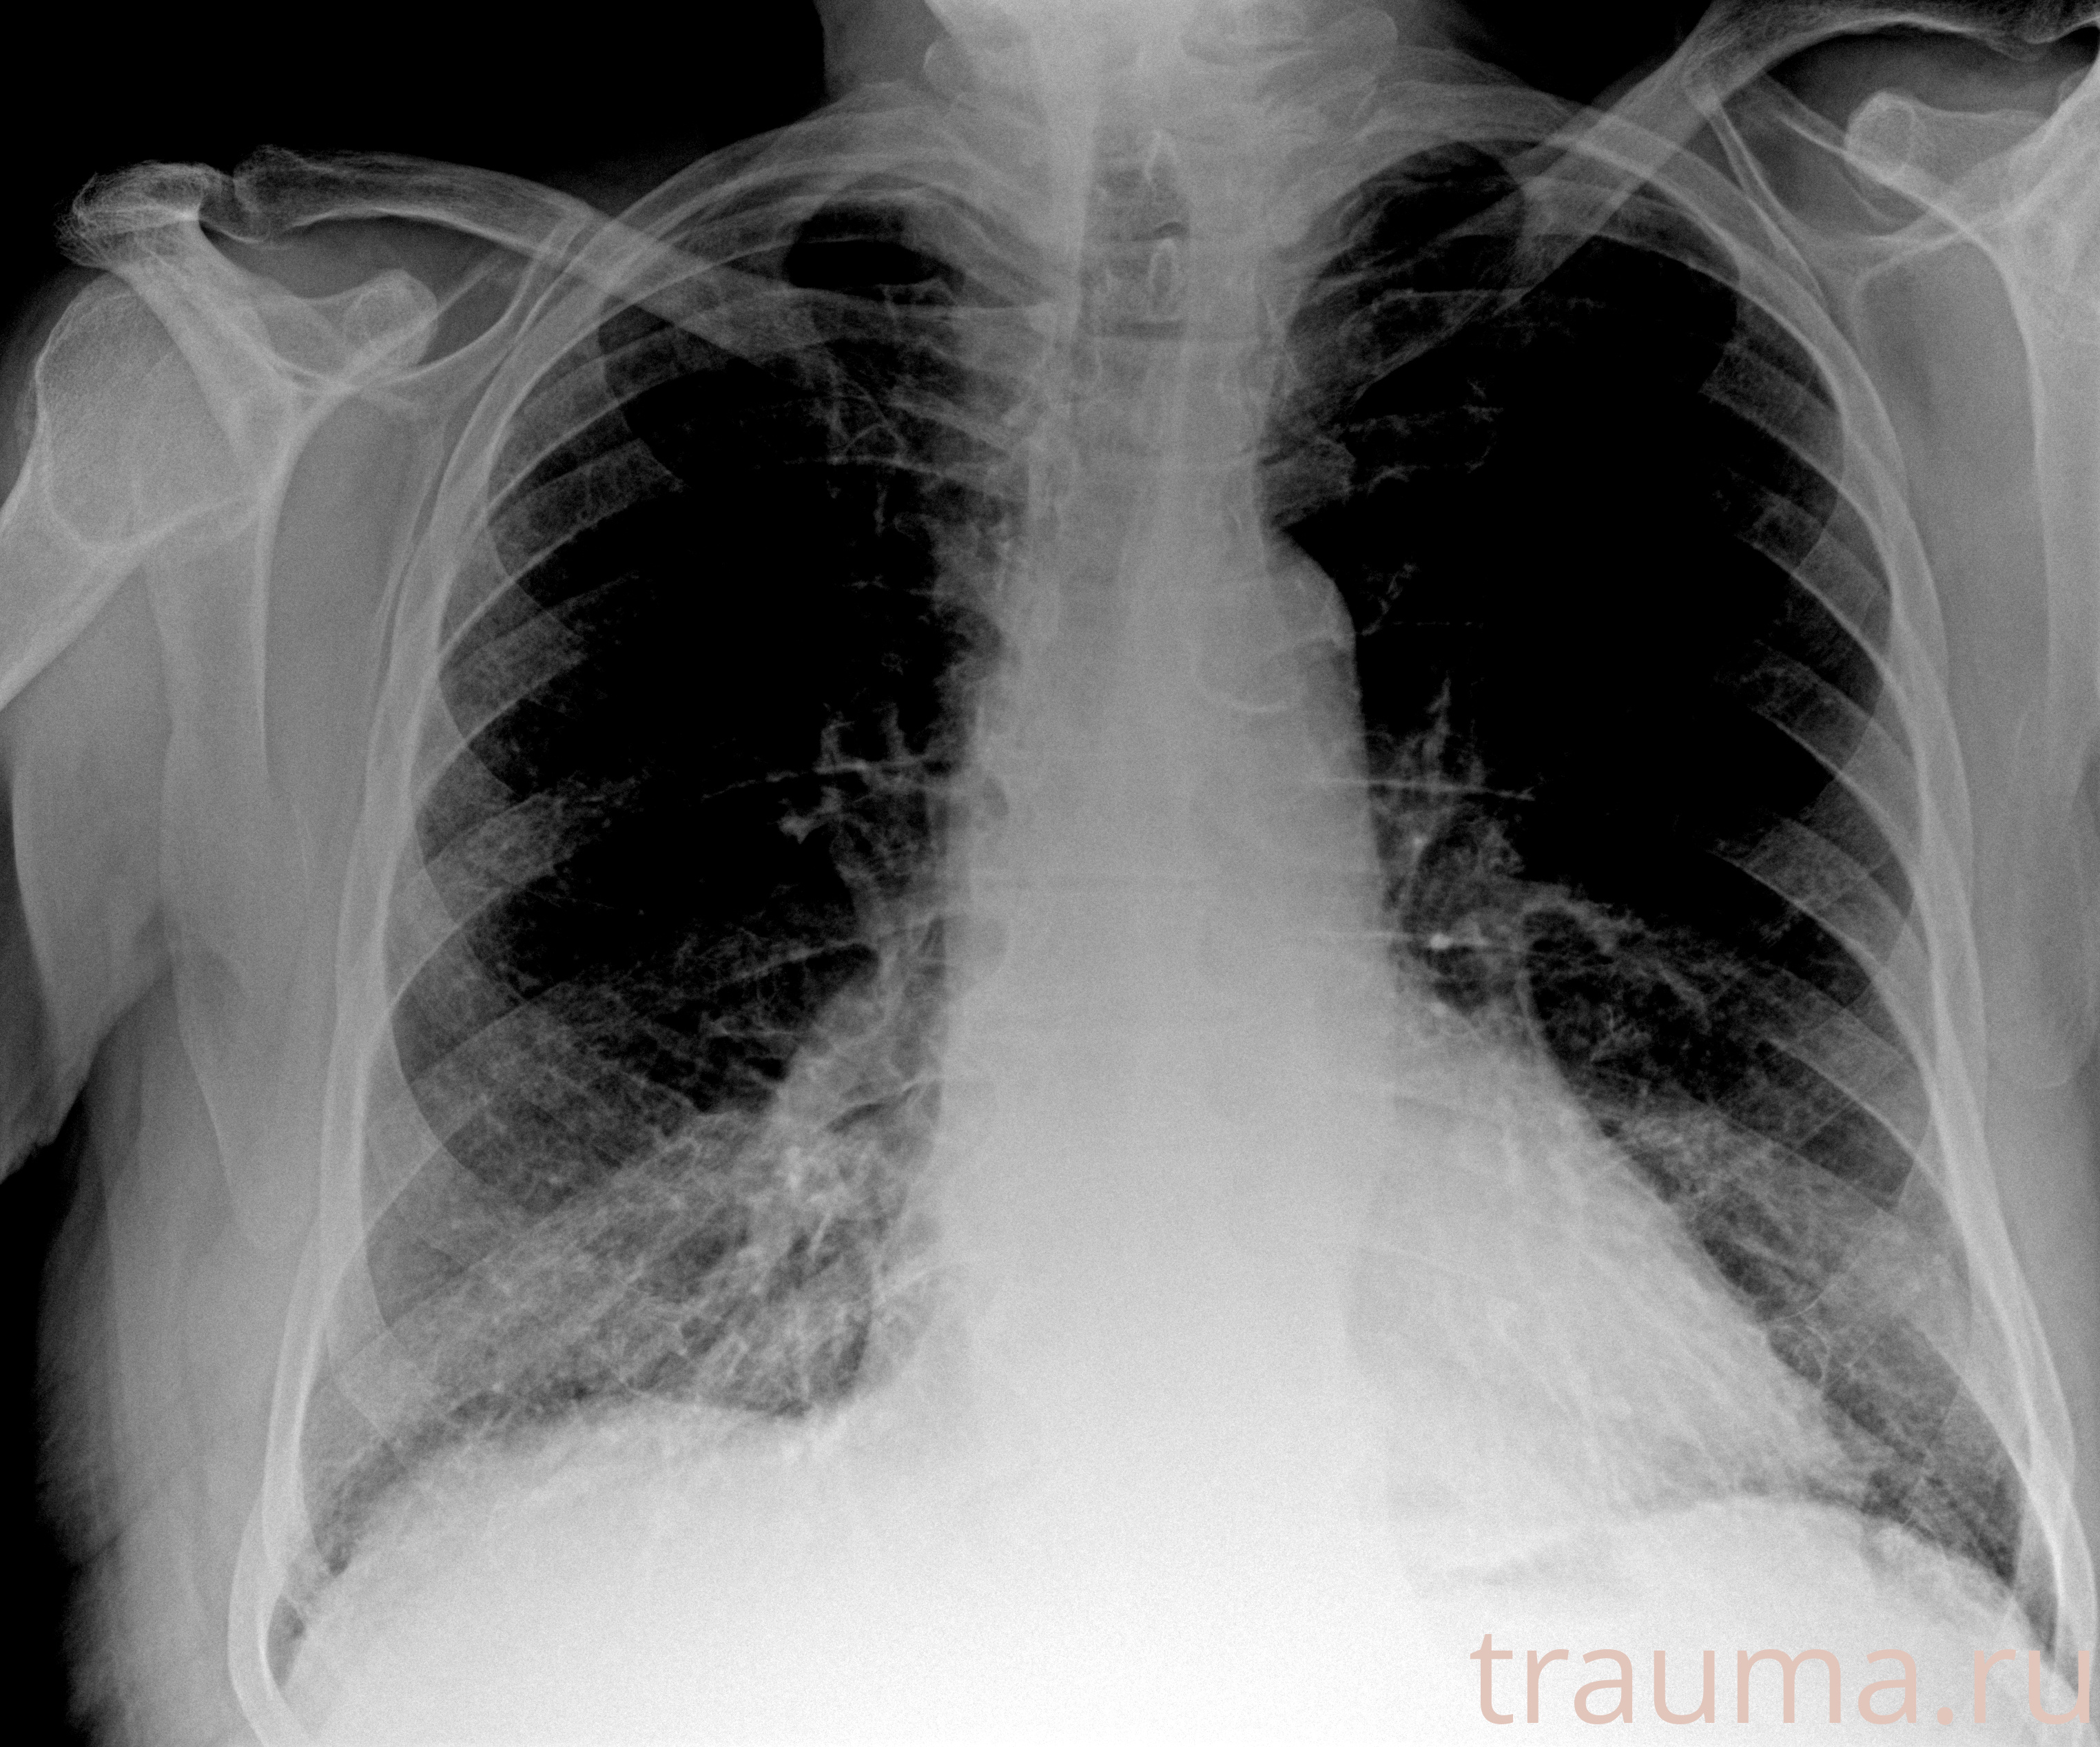

Рентгенограммы

Рентген на дому: по вашему адресу приезжает врач-рентгенолог, травматолог-ортопед с мобильным рентгеновским аппаратом, проводит диагностику травмы или заболевания, делает необходимые рентгенограммы, дает рекомендации по дальнейшему лечению. Получить качественные снимки в домашних условиях возможно благодаря уникальной методике, разработанной МосРентген Центром для института  Склифосовского

Яркость: 1   Контраст: 1   Инвертировать: 0 Увеличение: 1

Перетаскивайте мышь вверх/вниз для контраста, влево/право для яркости. Прокрутка колесом изменяет масштаб. Нажмите Сбросить для возврата к исходному изображению. При увеличении держите мышь в той области, которую хотите рассмотреть.